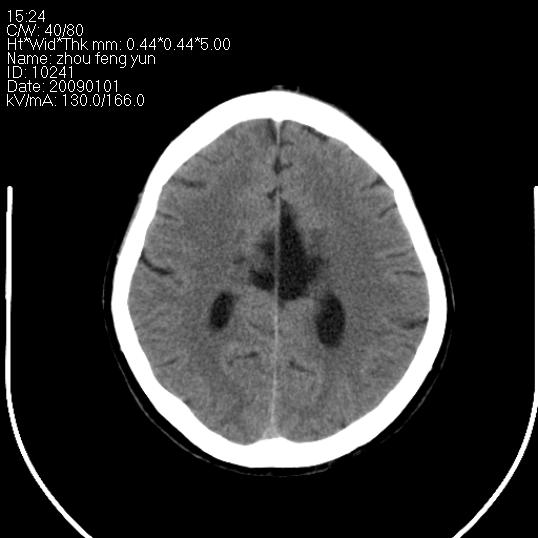

以下是引用hhcckk在2009-1-1 16:39:00的发言:[br]胼胝体嘴、膝部及部分体部发育不全,为囊状影替代,两侧侧脑室分离,脑室后角扩张[br][br]诊断:胼胝体发育不良[br][br]胼胝体发育不良(dysgenesis of the corpus callosum)是最常见的颅脑畸形,是胚胎期背部中线结构发育不良的一种形式。主要包括胼胝体缺如和部分缺如。胼胝体发育不良还可合并其他畸形,如胼胝体脂肪瘤、蛛网膜囊肿、脑膨出、chiari畸形、灰质异位症、脑回畸形等。[br][br]ct诊断要点:[br]1. ct横断扫描可见两侧侧脑室明显分离,脑室后角扩张,形成典型的蝙蝠翼状侧脑室外形。[br]2. 第三脑室扩大并向上插入两侧脑室体部之间,严重者第三脑室可上移到两侧大脑半球纵裂的顶部。在ct冠状扫描位显示更清。[br]4. 胼胝体畸形常伴有脂肪瘤,可测到其特征性脂肪密度。部分脂肪瘤的边缘可出现线样钙化[br]